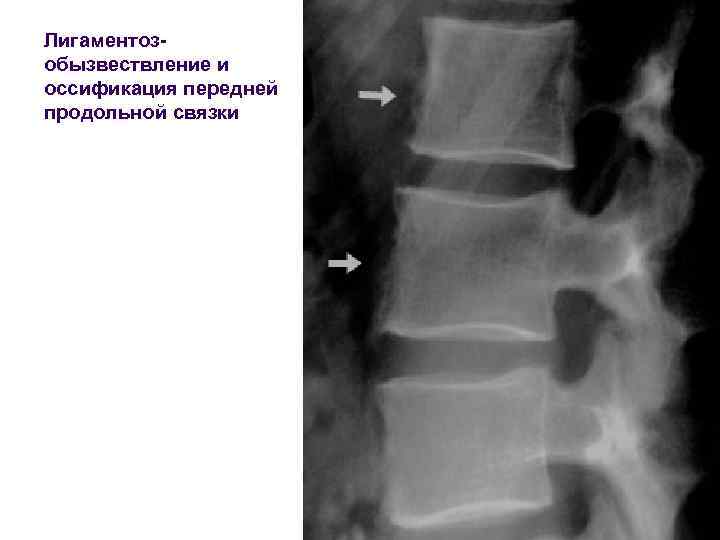

Лигаментозобызвествление и оссификация передней продольной связки